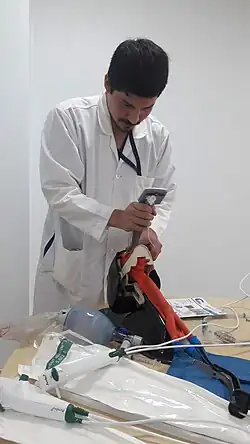

Anesthesiologist using the Glidescope video laryngoscope to intubate the trachea of a morbidly obese elderly person with challenging airway anatomy | |